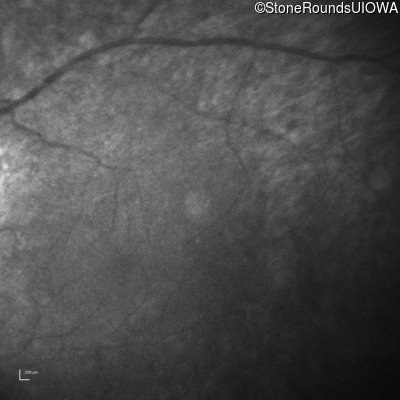

Infrared Fundus Photograph - Left -

No Light Perception

Light Perception